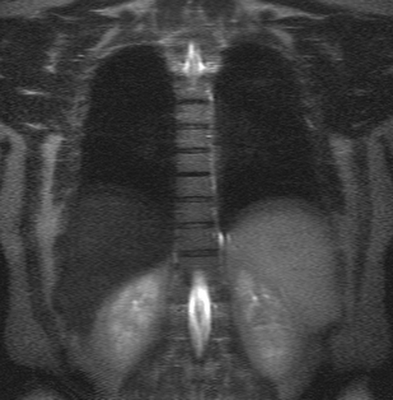

Ведущими в МРТ позвоночника всегда являются сагиттальная (вдоль тела) а аксиальная (поперечная) плоскости, дополнительной может быть корональная (фронтальная) плоскость. Физические основы МРТ и получение МРТ изображения изложены в наших статьях, однако, они предназначены для подготовленного читателя. Разглядывая МРТ изображение позвоночника, Вы увидите, что спинномозговая жидкость (ликвор) на одних из них светлый (почти белый), на других, наоборот, темный. Так можно различить Т2-взвешенные и Т1-взвешенные МРТ изображения. Очень важно понимать, что это не негатив и позитив, а МРТ изображения, зависимые от разных физических характеристик, и потому несущие в себе разную информацию. На снимке (вернее сказать, отпечатке) или на CD диске, сняты или записаны серии однотипных по способу получения МРТ изображений позвоночника. Срезы идут друг за другом, например, справа налево в сагиттальной плоскости. Обычно для облегчения понимания где проходит данный срез в углу картинки дается референтное изображение, оно показывает линию этого МРТ среза в другой, перпендикулярной ему плоскости. Иногда делается дополнительное референтное МРТ изображение на котором показаны все срезы с их нумерацией. Зазор между срезами меньше 1 мм или вовсе отсутствует. Толщина среза выбирается оптимальной в зависимости от исследуемого отдела позвоночника, плоскости и МРТ аппарата. Обычно при МРТ позвоночника она 3-4 мм. В любом случае, выбираемый оператором или врачом протокол МРТ (то есть набор плоскостей и последовательностей), соответствует задачам данного МРТ исследования. Оценка качества МРТ изображения не может быть осуществлена ни пациентом, ни врачом-клиницистом. Заключение, данное врачом-рентгенологом, подразумевает, что само изображение было приемлимым для выводов. Хотелось бы особо подчеркнуть, что Заключение в конце Описания, выдаваемое пациенту, не является диагнозом, а лишь выводами врача- рентгенолога на основе интерпретации им изображений. Диагноз ставится врачом-клиницистом на основании всех имеющихся медицинских данных - жалоб, клинического осмотра, заключений других специалистов, лабораторных анализов, заключений по МРТ и другим изображениям. При этом расхождения между заключениями по результатам разных исследований явление вполне нормальное.

Шейный и поясничный отделы у человека максимально подвижны, поэтому большинство патологических процессов локализуется в данных областях. МР-снимок визуализирует позвоночник в трех плоскостях: аксиальной, коронарной (фронтальной) и сагиттальной. Одна из них, в зависимости от характера подозреваемой патологии, основная, две другие - уточняющие. Возможность разносторонней оценки множества срезов толщиной от 1 мм позволяет выявить болезнь на стадии формирования. Если при расшифровке результатов МРТ позвоночника нет пороков развития, суставы и диски расположены на своем анатомическом месте, имеют нормальную структуру без костных разрастаний, нарушение кровоснабжения спинного мозга отсутствует - все в порядке.